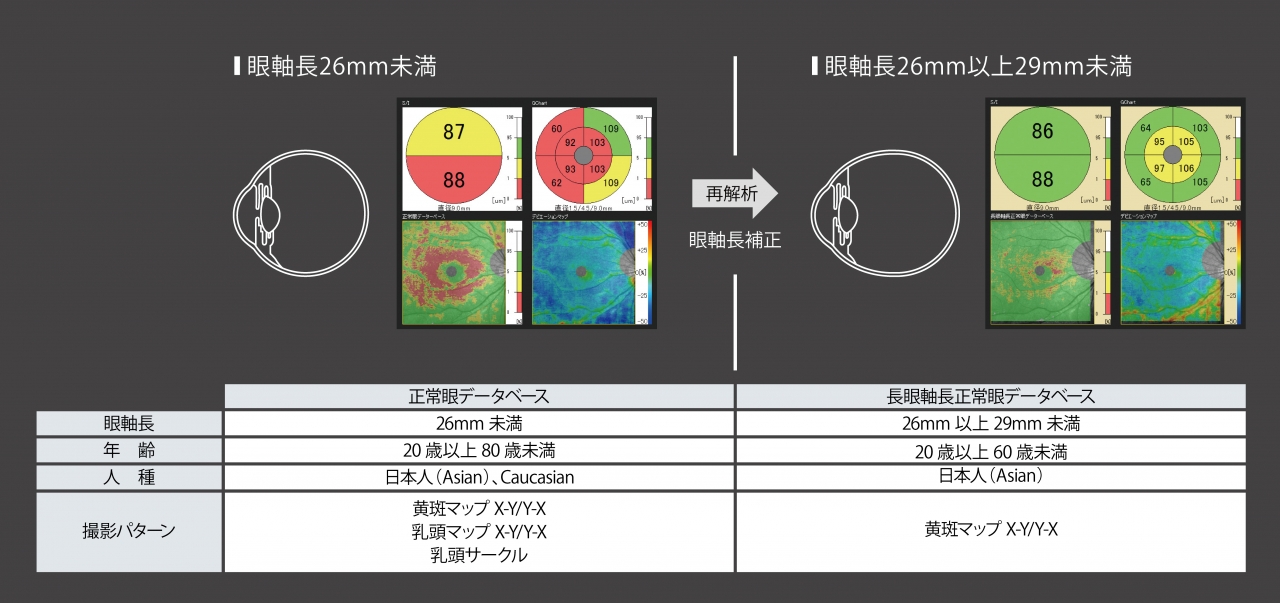

- 長眼軸長正常眼データベースを搭載(オプション)

長眼軸長正常眼データベースを搭載(オプション)